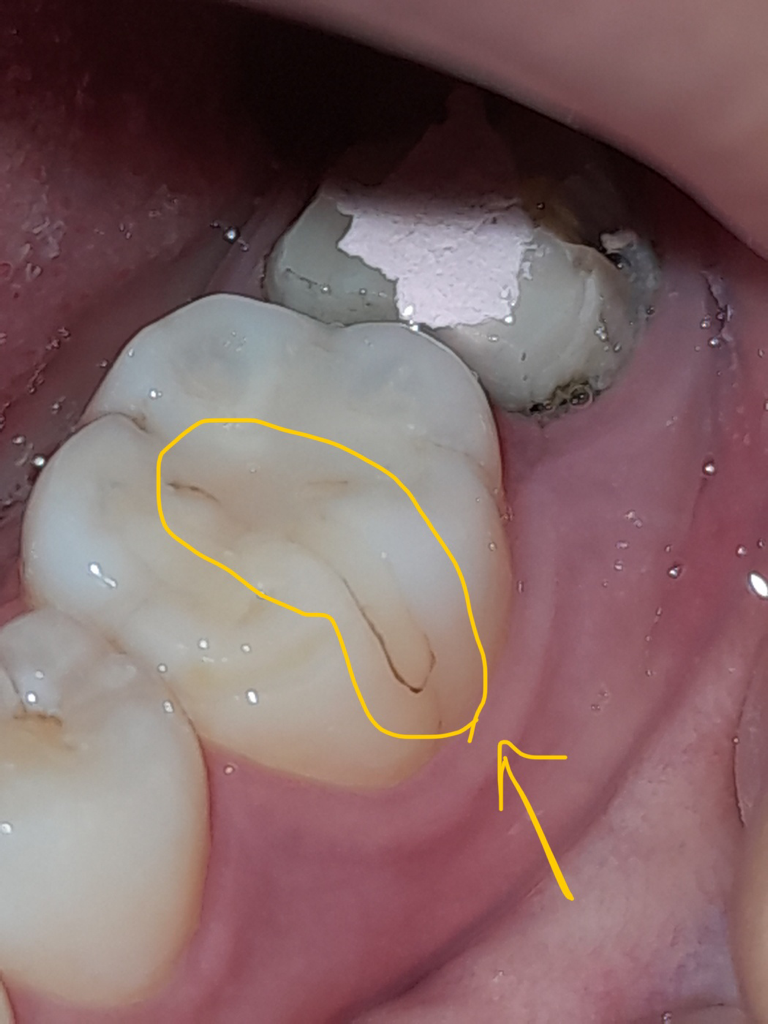

오늘 어금니 크라운 제거 후,

안에 있던 충치 긁어내고 소독, 신경치료 했는데요.

치료 받은 옆 어금니에 원래 크랙이 없었던 거 같은데...

크라운을 제거하는 중에 저렇게 됐나 싶어서요.

근데 또 크랙난 부분이 갈색이라

이미 나있던건가 싶으면서도,

치아 살피면서 처음 보는 거 같아서..

치료 중에 난 피나 충치 파낸 게 낀건가 싶기도하고..

모르겠네요ㅠㅠ

• 1번 째 사진

검은 부위는 크랙이 아니고 아래쪽으로 나있는 희미한 선이 크랙인것으로 보입니다.

크랙이 있는 경우 충전재의 틈이 이격되면서 해당부위로 착색이 될수 있어요.

저부위는 크랙간게 아니라 예쩐에 치료받은부분이 변색된거 같습니다. 사진상으로 봐도 크랙이 보이거나 그렇진 않습니다.